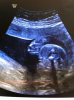

Voilà à la 2nde écho et à celle de vendredi dernier ^^

photo(1).jpgphoto(2).jpg

rholala, faut regarder où sur la 1ère image ???

Sur la 2ème, yen a des traits blancs didonc, elle a plein de pas-nouilles ta mini-toonette :p

Sur la 1ère ce sont les 2 traits blancs les lèvres. Et sur la 2nde, il m'a fait un gros plan ^^